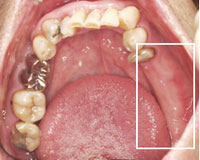

治療前の下の歯

右上の奥歯と左下の奥歯を失っているので、抜けた部分にどんどん歯が倒れかかっていき全体の歯並びを大きく崩し物を咬めない状態。キチンとかみ合わせる大黒柱がない。